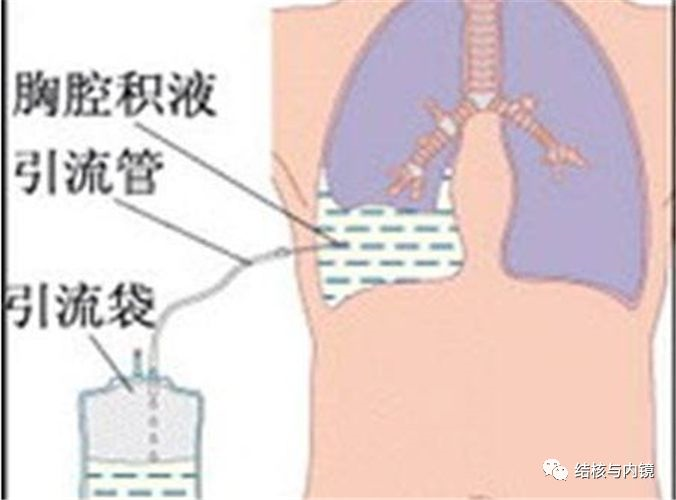

胸腔镜诊断结核性胸膜炎

引起胸腔积液的原因很多,部分胸腔积液患者常规检查不能确诊,而采用内科胸腔镜可以直接窥视病灶,检查范围广,易操作,同时多部位多点活检,明显提高诊断准确率,有报道可达 92%-100%。